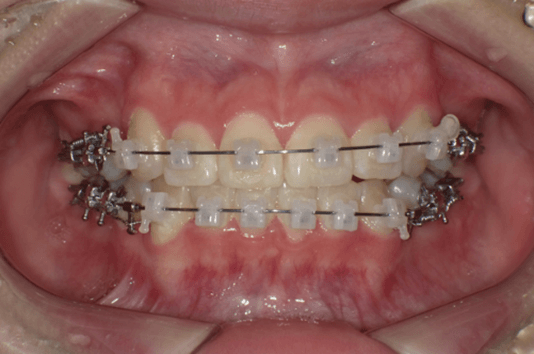

●3か月後

左上の空隙がほぼ閉鎖し、上下顎の正中が合ってきている。(写真b)